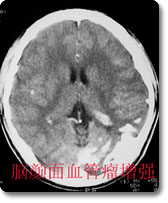

中枢神经影像诊断是本科室的特色、强项诊断之一,尤其是现代影像学诊断,如CT、MRI等,是西南地区最早开展此项工作的单位,积累了丰富的临床经验,有较高的诊断水平。如对脑肿瘤的影像学表现和肿瘤分子生物学基础的对照研究、脑血管病的诊断和介入治疗等在国内处于领先地位。 |